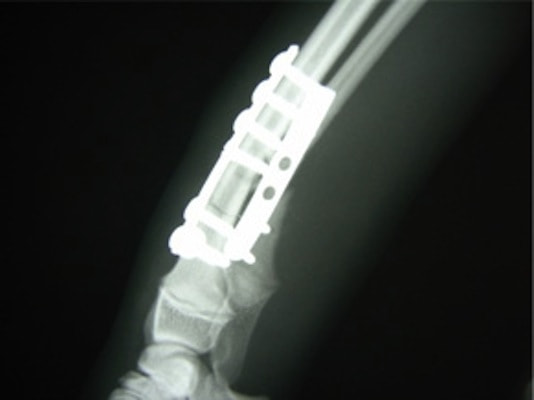

Advanced Locking plate system と Locking compression plate system

当院ではAdvanced Locking plate system(ALPS)と、Locking compression plate system(LCPS)という骨接合法で骨折症例の治療を行っています。

Advanced Locking Plate System

従来型のプレートのように広い面積で骨と接するプレートを用いて固定を行った場合、プレート下の骨はプレートとの接触面において血行が絶たれ壊死し、それがリモデリングされると骨密度が低下する。この骨密度の低下防ぐために、骨折部局所への血行を温存することの重要性が近年改めて認識されるようになってきている。Advaed Locking Plate System (ALPS)は従来型のプレートシステムの欠点を改良し、より使いやすく、より骨への血行を阻害しないようにというコンセプトで作られた。

Advanced Locking Plate System の特徴

- 骨への血行障害は最小限である

- 上下左右にベンディング可能でより3次元的な成形が可能

- すべての部位においてプレート強度は均一である

- ロッキングスクリューと圧着型スクリュー(皮質骨スクリュー)の双方が使用できる

- ダイナミックコンプレッション機能

- 生体親和性の高いチタン製

- トイ犬種から馬まで応用できるサイズ展開がある

トイプードル 右遠位橈尺骨短斜骨折のALPSによる内固定